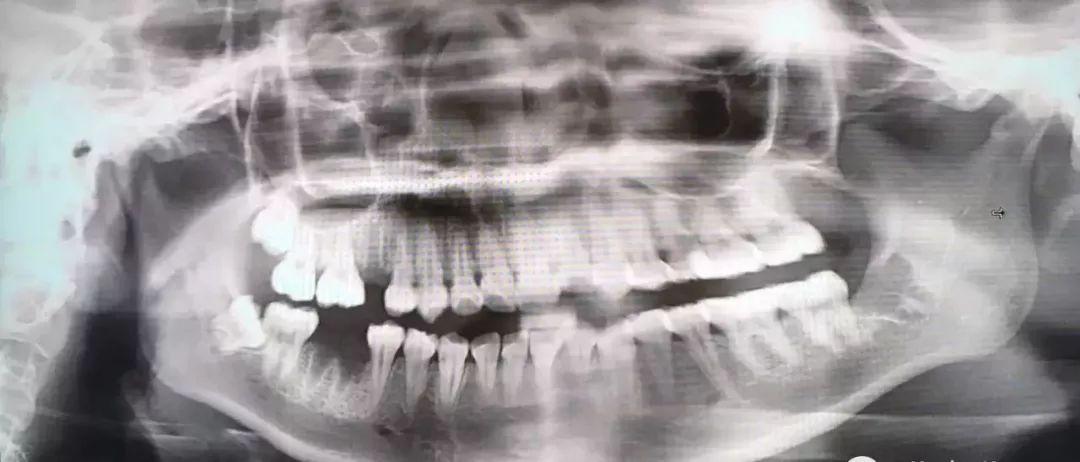

噩梦模式

最后介绍一下,牙根弯曲,骑在下颌管上的智齿...由于下颌管内神经丰富,拔除的时候需要极度小心,而且看长相也知道这种模式的拔牙,非常难也非常贵!

也是先切开牙肉,翻开并露出骨头,切下牙冠后取出,再处理下面的牙根。

把牙根分成两半,根据牙根的走向,分别小心地撬出来,这个过程十分考验技术,要谨慎避免损伤到下颌神经...